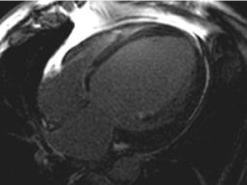

Es la prueba diagnóstica más valiosa y se ha de realizar siempre que se sospeche esta enfermedad.

Los hallazgos principales son los siguientes:

- Hallazgo típico: dilatación de las cavidades afectadas y su forma esferoidal, especialmente del ventrículo izquierdo.

- Las paredes están adelgazadas.

- Disminución difusa de la función contráctil.

- Pese a que la fracción de eyección suele estar baja, el gasto cardíaco en estos pacientes puede ser normal. Esto se debe a que los volúmenes de eyección están muy aumentados y además existe una taquicardia compensadora.